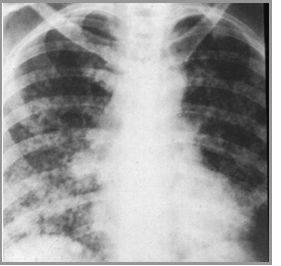

Coccidiomycosis

© Gower